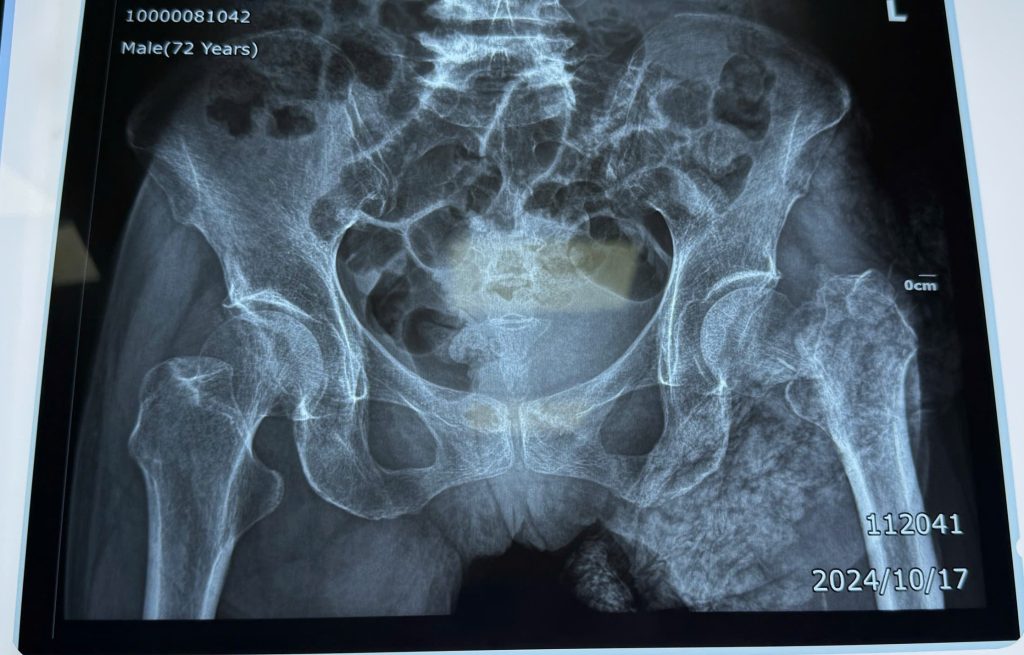

Các bác sỹ Trung tâm Y tế huyện Yên Lập đã tiếp đón, đánh giá và nhận định tình trạng của người bệnh. Kết quả chụp X-Quang cho thấy, bà T bị gãy cổ xương đùi, gãy ngành ngồi trái, gãy đầu dưới xương quay trái có di lệch và trật khớp xương trụ trái.

Nhận định tình trạng khá phức tạp, nặng nề, Y bác sĩ của Khoa Ngoại tổng hợp – Chuyên khoa đã trực tiếp hội chẩn cùng các chuyên gia của Bệnh viện Đa Khoa tỉnh Phú Thọ, thống nhất chẩn đoán: Người bệnh T. bị gãy cổ xương đùi trái di lệch và đưa ra phương án phẫu thuật thay khớp háng trái toàn phần.